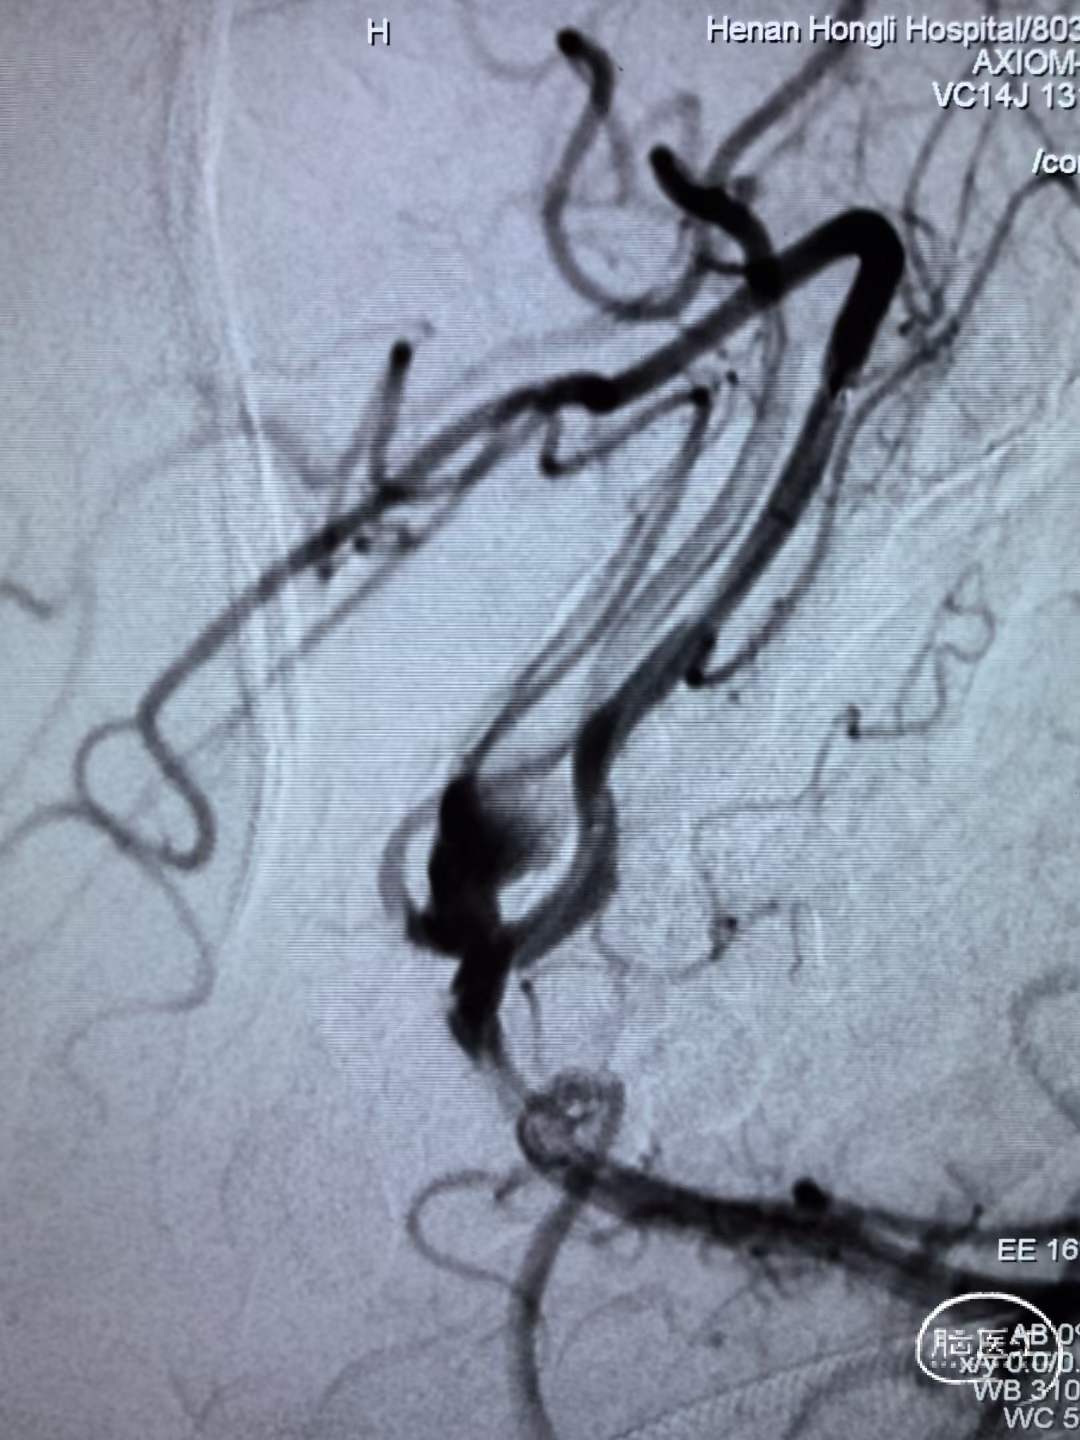

动脉瘤致密栓塞,载瘤动脉血流通畅。

术前术后对比